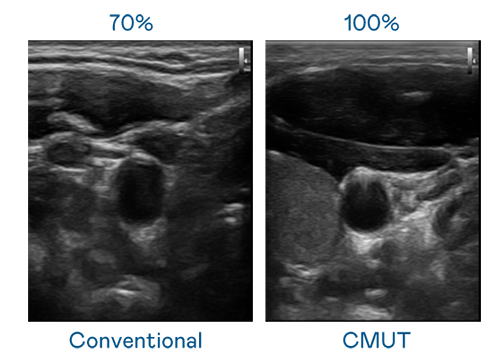

CMUT 技术是一种用电容式微机电元件来产生超音波讯号的技术。与传统 PZT 压电式技术相比,CMUT 频宽增加 30%,更宽频的超音波讯号让影像解析度大幅提升,是实现高影像品质医疗超音波扫描、促进精准医疗发展的关键技术。

大频宽带来超清晰影像

超音波影像的解析度高低,首先取决于探头能发出的讯号频宽。凤凰联盟 CMUT 可提供高清晰的超音波讯号,提供高频宽、高灵敏度、影像纹理细节更高的超音波影像,协助医护人员缩短影像判读时间及利用精准的医疗影像进行诊断。